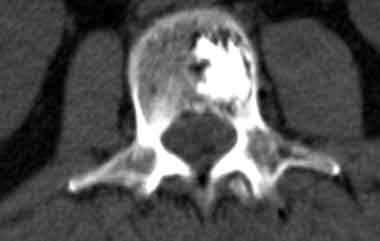

Проводим диагностику и лечение грыж любой формы межпозвонкового диска с помощью метода лазерной вапоризации.

Метод лазерной вапоризации выполняется, как правило, в амбулаторных условиях с использованием местной анестезии + внутривенное потенцирование. Чаще для местной анестезии используется 1% раствор лидокаина.

Под воздействием лазерного луча на конце световода создается высокая температура (от 200 до 400oС). Это приводит к образованию газа и пара, который выходит наружу через просвет иглы. При этом понижается внутридисковое давление, диск как бы сморщивается и грыжа, под действием возникающего «вакуум-эффекта», а так же, эластичности сохранившихся слоев фиброзного кольца и задней продольной связки, втягивается.

В этом и состоит основной смысл лазерной вапоризации или нуклеопластики. Как правило уже в процессе выпаривания больные отмечают уменьшения боли в пояснице.

Все вышеизложенные методы диагностики проводятся с помощью Мультисрезового спирального компьютерного томографа Toshiba (Asteion Super 4) - 26 декабря 2006 года выпуска, который находится на базе 19-й городской больницы.

Томограф фирмы TOSHIBA позволяет не только ставить точный диагноз, но и эффективно лечить пациентов: являясь новатором в технологии КТ, фирма TOSHIBA первая разработала возможность КТ – рентгеноскопии в реальном времени ( КТ – флюороскопия). КТ – это навигация в реальном времени, т.е. специальная флюороскопическая программа дает хирургу возможность проводить пункцию или пункционную биопсию образований, следя за продвижением иглы на экране томографа в реальном времени. Это полностью исключает нежелательное повреждение жизненно важных структур и обеспечивает точность попадания в заданную цель с точностью до 1 мм. Уже сегодня специалисты Центра Эндоскопической нейрохирургии, первыми в Украине, успешно делают бескровные пункционные операции на позвоночнике под контролем компьютерного томотрафа, так называемые пункционная вертебропластика – это когда под контролем томографа в тело поражённого позвонка вводится специальный костный цемент, который через несколько минут застывает. Это эффективный метод предупреждения и лечения патологических переломов позвонков при гормональном остеопорозе и гемангиоме тел позвонков.